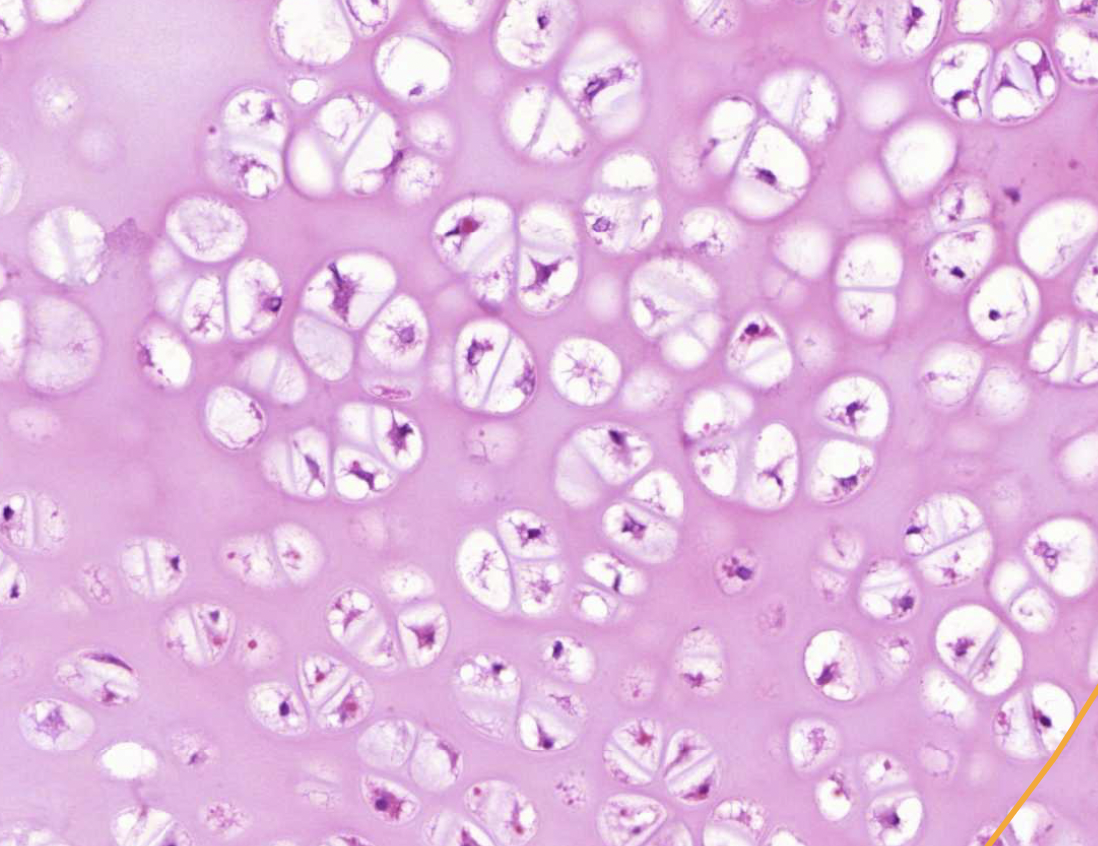

term image

chondrocytes - secrete cartilage matrix